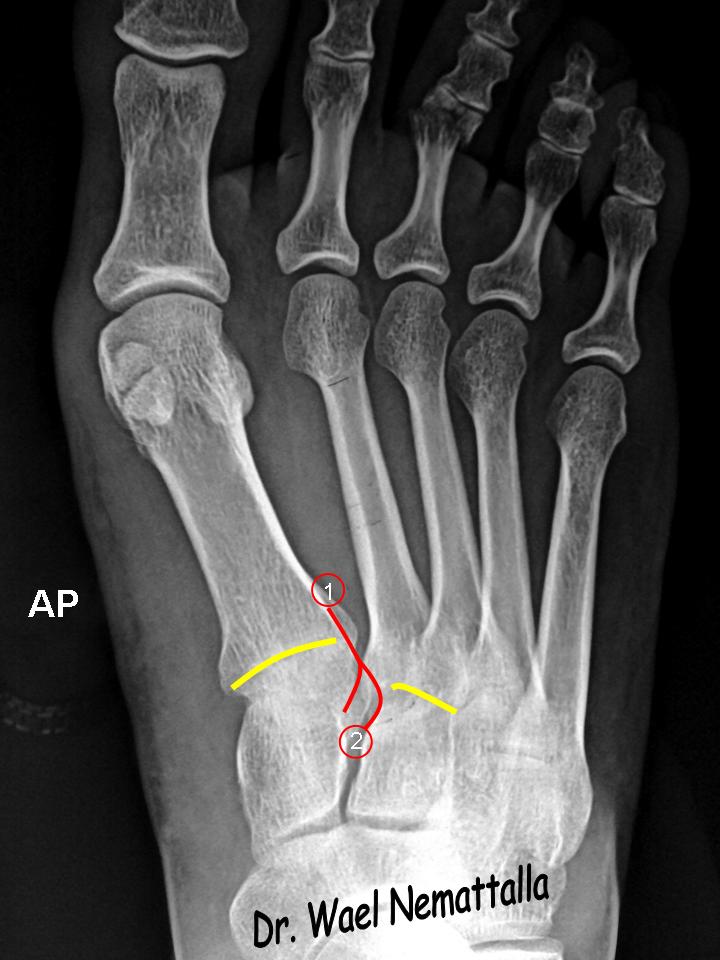

Анатомия суставов Шапарова и Лисфранка: фото и информация

Раздел: Мудрость в деталях